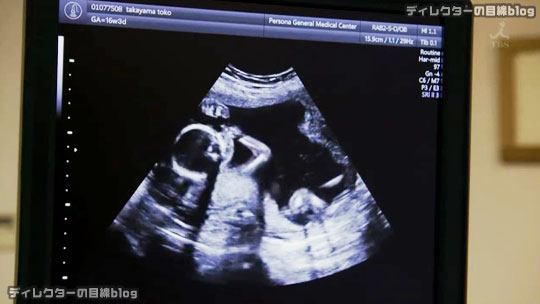

サクラ(綾野剛)は羊水検査を希望する妊婦・透子(初音映莉子)を診察する。透子は別の病院で出生前診断を受け、おなかの子がダウン症候群の可能性が高いと診断されていた。サクラはまだ現実を受け止めきれない透子と夫・光弘に、検査の結果が出る前に今後どうするかを話し合っておくよう語りかける。一方、やはりおなかの子がダウン症候群と診断された信英・明代(りょう)夫妻。2人は長女のことや生活のことを考え、中絶を希望する。

既にここ↑まで書いてしまったから、1組目の夫婦・高山夫妻についてこれ以上言及することは余りないのだが、演出と演技の観点でとても興味深い部分がある。羊水検査のためにペルソナを訪れた高山夫妻に、赤ちゃんが好きなサクラだからこそ掛ける言葉がジーンと心に響くシーンだ。